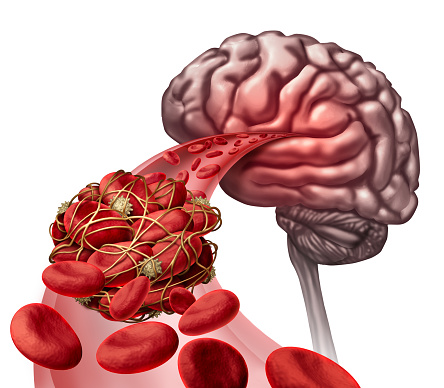

It’s important to keep your brain healthy, especially as you age. Mental decline is one of the most common symptoms of aging and it inflicts most, if not all, elderly people. With the elderly population on the rise, it’s important to promote a healthy brain. Most people get the feeling sometimes that they can’t forget ...click here to read more